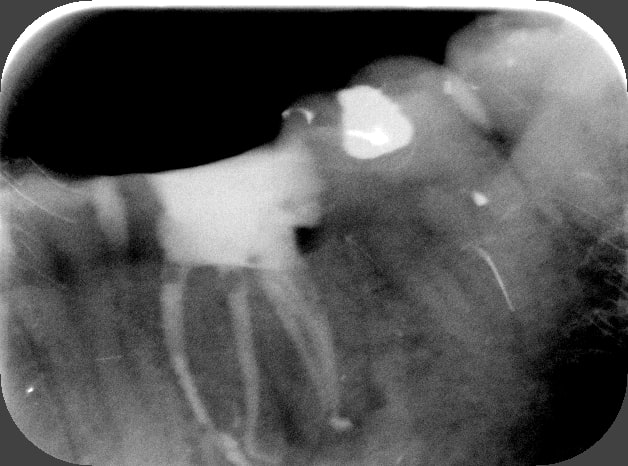

C'est quoi la proba d'avoir une deuxième bio à 5 canaux en 2 semaines?

(la radio excentrée est dégueulasse, mais ça montre les doubles courbures, quelques peu minimisées par l'angulateur...